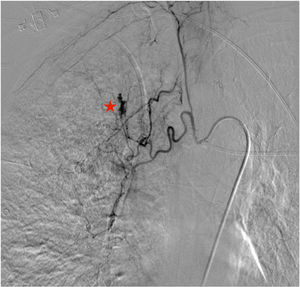

A 70-year-old woman was admitted to our intensive care unit due to COVID-19 pneumonia. She received treatment with remdesivir for five days, two doses of tocilizumab and methylprednisolone (1mg/kg/day). Patient required intubation and tracheostomy due to myopathy. After nineteen days, patient presented a massive hemoptysis. An urgent bronchoscopy evidenced a non-occlusive clot in the right main bronchus and a pulsatile lesion underneath. The pulmonary artery angiography showed a pseudoaneurysm in a right intercostobronchial trunk (Fig. 1) with extravasation of iodinated contrast (red star). Immediate transcatheter exclusion of the pseudoaneurysm was successful. The thoracic CT-scan evidenced the typical COVID-19 pattern with a highly suspicious aspergillus cavity (red arrow) in the right upper lobe pulmonary parenchyma (Figs. 2 and 3). Respiratory secretions cultures were positive for Aspergillus niger so dual antifungal treatment was started. This case illustrates the risk of COVID-19 associated pulmonary aspergillosis (CAPA) and related complications.